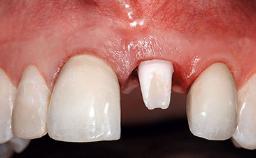

A 32-year-old female Caucasian patient with a compromised maxillary right central incisor was referred to us by a general dentist. Her chief complaints were discomfort and mobility of tooth 11 with unsatisfactory esthetics due to discoloration. The patient reported a previous trauma, some years earlier, as the origin of pathology on the afflicted tooth. Anamnesis was negative for any other dental or periodontal pathology in the remaining dentition. The patient did not take any medication and reported to be a light smoker (5–10 cigs/day). She had high esthetic expectations of her treatment. The extraoral examination revealed a high smile line with full exposure of her maxillary teeth and surrounding soft tissue in the area between the second premolars.

| Placement Protocol | Early or late implant placement |

| Interim Prosthesis during Healing | Fixed Fixed |